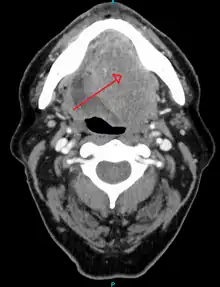

Diagnosis

Diagnosis of oral cancer is completed for (1) initial diagnosis, (2) staging, and (3) treatment planning. A complete history, and clinical examination is first completed, then a wedge of tissue is cut from the suspicious lesion for tissue diagnosis. This might be done with scalpel biopsy, punch biopsy, fine or core needle biopsy. In this procedure, the surgeon cuts all, or a piece of the tissue, to have it examined under a microscope by a pathologist.[33] Brush biopsies are not considered accurate for the diagnosis of oral cancer.[34]

With the first biopsy, the pathologist will provide a tissue diagnosis (e.g. squamous cell carcinoma), and classify the cell structure. They may add additional information that can be used in staging, and treatment planning, such as the mitotic rate, the depth of invasion, and the HPV status of the tissue.

After the tissue is confirmed cancerous, other tests will be completed to:

- better assess the size of the lesion (CT scan, MRI or PET scan with 18F-fluorodeoxyglucose (FDG)),[33]: 143

- spread to the lymph nodes (CT scan) or